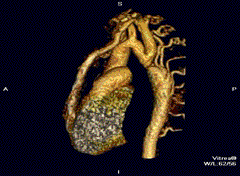

Coarctation of the aorta can be accurately diagnosed with magnetic resonance angiography. In teenagers and adults echocardiograms may not be conclusive.

The severity of coarctation of the aorta can be rated by a combination of the smallest aortic cross-sectional area of the aorta (adjusted for body surface area) as measured by 3D-rendered contrast MRI, as well as mean heart rate–corrected flow deceleration in the descending aorta as measured by phase contrast magnetic resonance imaging.[9]